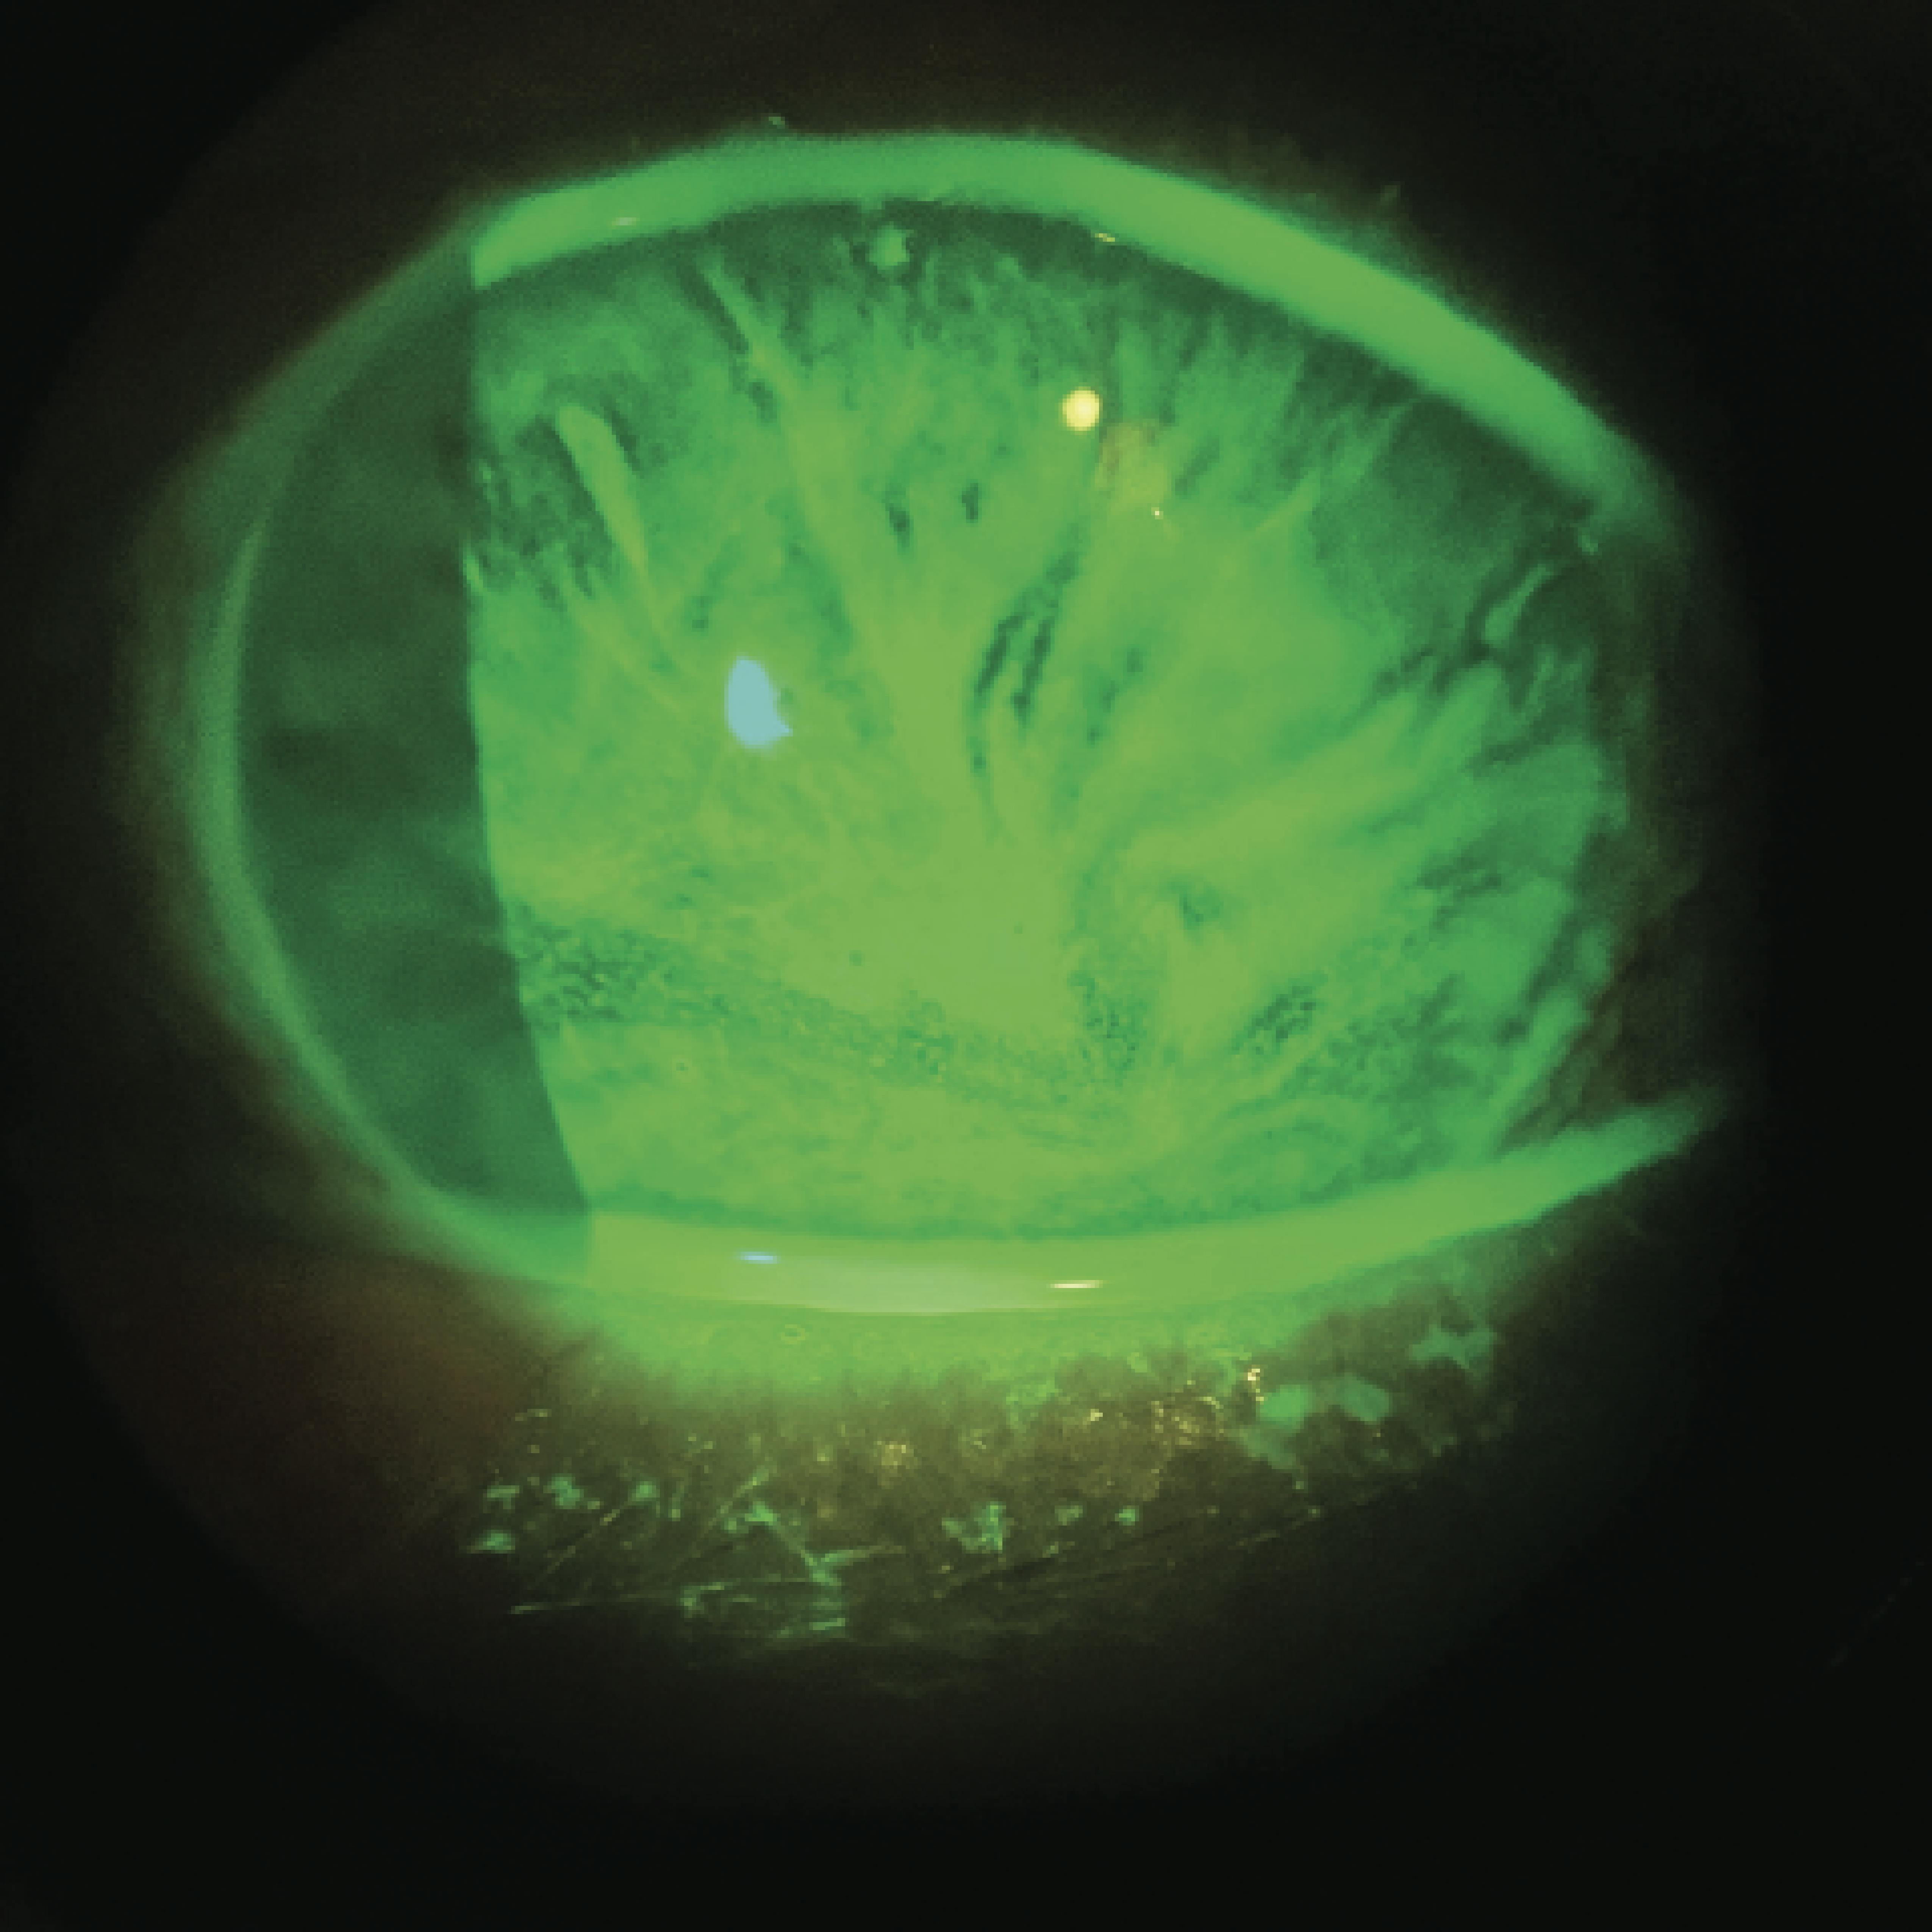

In recent years, our profession has seen remarkable advances in the treatment of corneal blindness, from procedures such as Descemet stripping automated endothelial keratoplasty and Descemet membrane endothelial keratoplasty, to keratoprosthesis and emerging cell-based therapies. Despite these breakthroughs, many patients with limbal stem cell deficiency (LSCD; Figure) remain inadequately treated. This is a significant concern, especially when we have well-established protocols for managing LSCD with ocular surface stem cell transplantation (OSSTx) combined with systemic immunosuppression (SI), which have been documented in peer-reviewed journals for more than 3 decades.1-4 However, these treatments are underused, and many patients are referred to centers that do not specialize in them.1